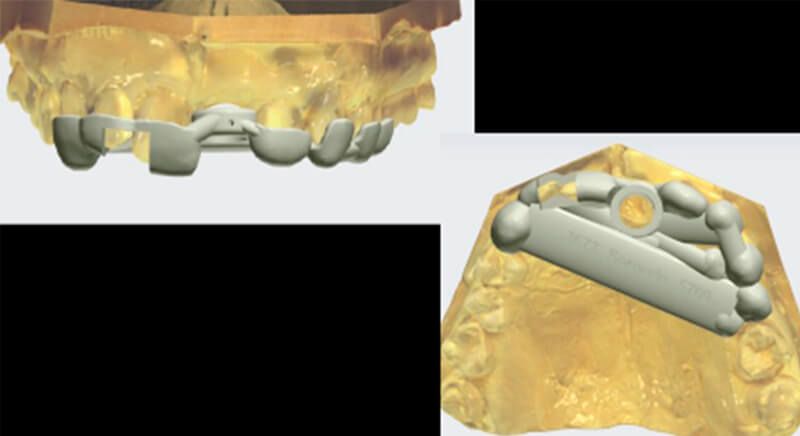

During the digital planning for the implant, with Implant Studio (3Shape) guided surgery software, significant bone defects due to the patient's anatomy were discovered. Placing the implant in the correct position for the prosthesis presented bone dehiscence in the vestibular area, and another bone defect in the palatine area due to the patient's large nasopalatine canal.

This information enabled us to rule out the option of surgery without a flap, as regeneration simultaneous to surgery would be needed, so the idea of using guided surgery was maintained.

The guided surgery was performed by lifting a full thickness mucoperiosteal flap. A Biomimetic Ocean CC implant, diameter 3.5mm and length 10mm, was inserted using the surgical guide in the ideal three-dimensional position and the defects were regenerated with xenograft and reabsorbable membrane, the nasopalatine duct on the palatine side and the area of dehiscence on the vestibular.